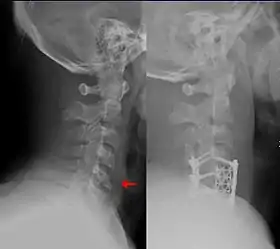

Teardrop fracture of the cervical spine before and after treatment with metal fixation

A flexion teardrop fracture is a fracture of the anteroinferior aspect of a cervical vertebral body due to flexion of the spine along with vertical axial compression.[1] The fracture continues sagittally through the vertebral body, and is associated with deformity of the body and subluxation or dislocation of the facet joints at the injured level.[2] A flexion teardrop fracture is usually associated with a spinal cord injury, often a result of displacement of the posterior portion of the vertebral body into the spinal canal.[3]